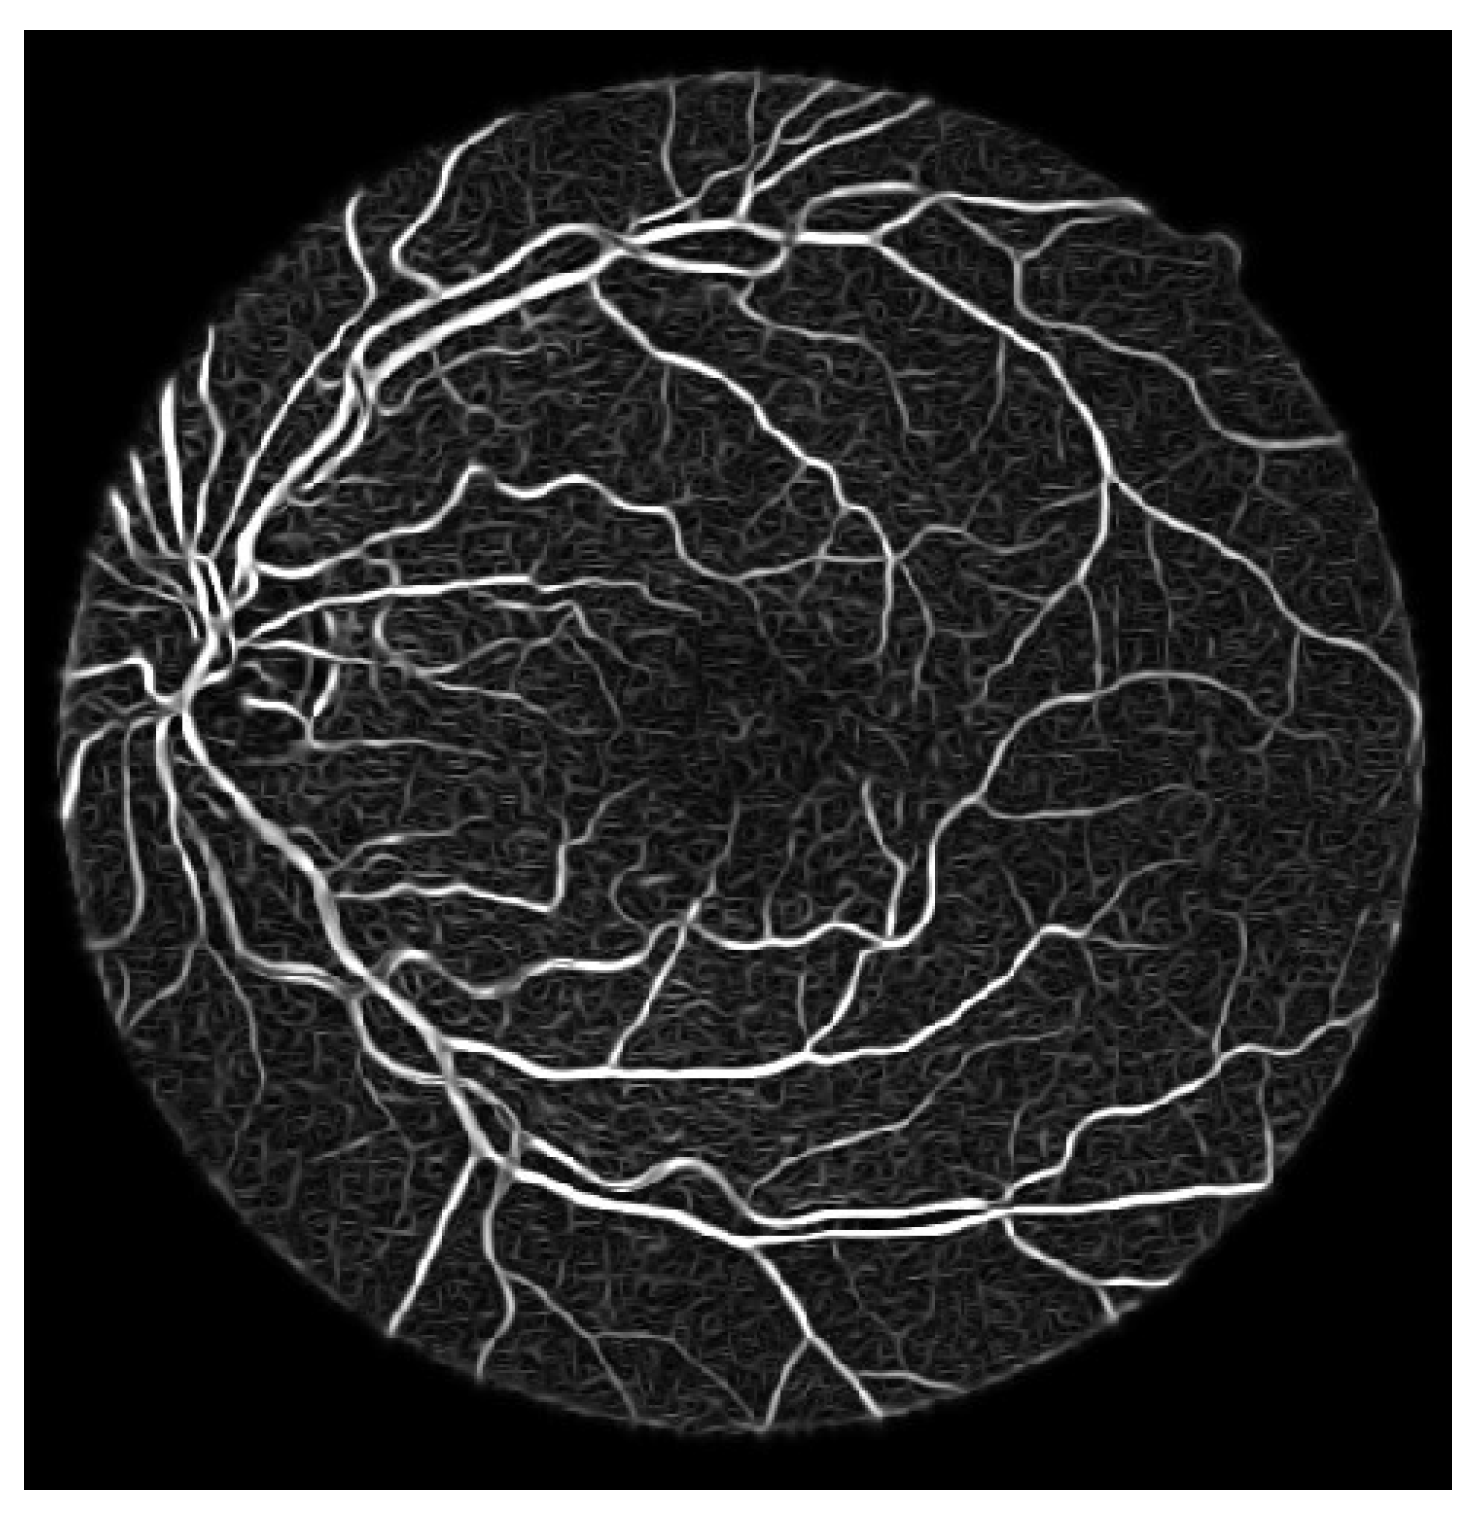

- Process the updated image based on the difference formula depicted equation below and achieved coherent vessels image as shown in Figure 11

- The fourth step is based on analyzing the normalization of vessels, especially tiny vessels, and it is an essential factor in increasing vessels’ sensitivity. The second-order detector is used to normalize the vessels, and there is still varying intensity of the vessels and broken ridges. This problem is addressed using anisotropic oriented diffusion filtering.